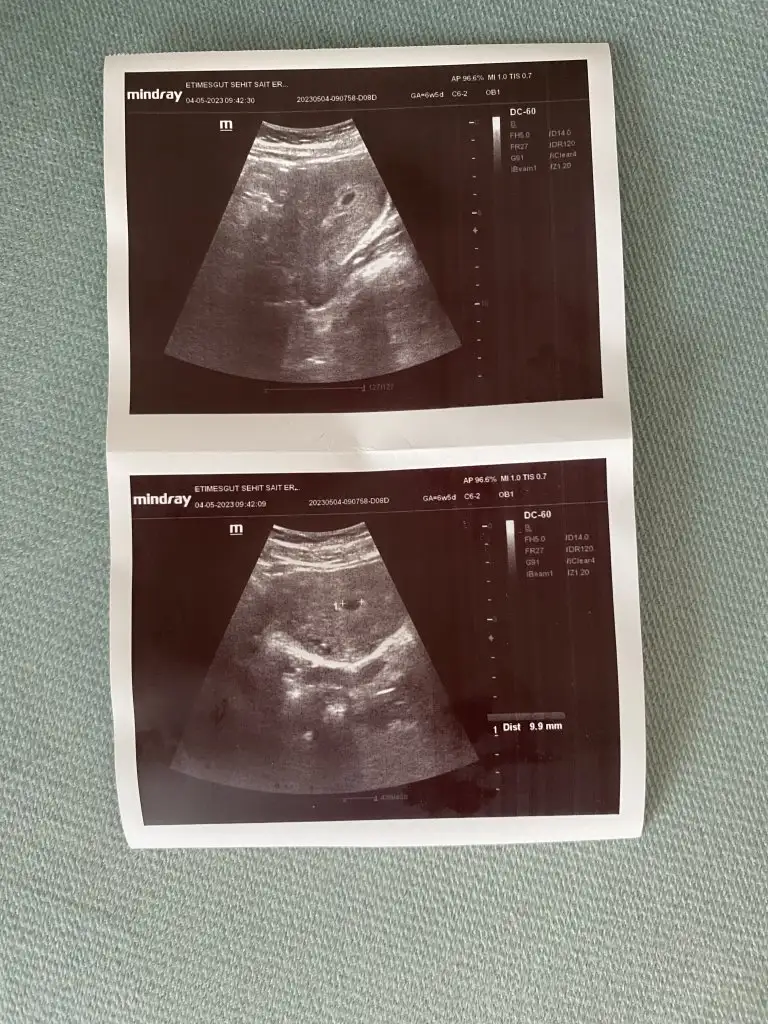

ne kadar geride demedi doktor 6+5de kese 9 mm geldi haftana göre küçük 15gün sonra gel dedi bebek falan da yok tabı ultrasonu ekledimYok dollendigi

ne kadar geride demedi doktor 6+5de kese 9 mm geldi haftana göre küçük 15gün sonra gel dedi bebek falan da yok tabı ultrasonu ekledim